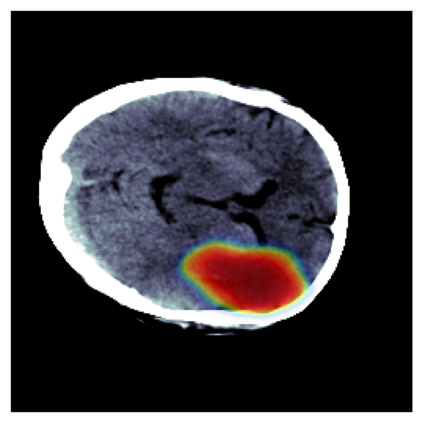

The sigmoid activation is the standard output activation function in binary classification and segmentation with neural networks. Still, there exist a variety of other potential output activation functions, which may lead to improved results in medical image segmentation. In this work, we consider how the asymptotic behavior of different output activation and loss functions affects the prediction probabilities and the corresponding segmentation errors. For cross entropy, we show that a faster rate of change of the activation function correlates with better predictions, while a slower rate of change can improve the calibration of probabilities. For dice loss, we found that the arctangent activation function is superior to the sigmoid function. Furthermore, we provide a test space for arbitrary output activation functions in the area of medical image segmentation. We tested seven activation functions in combination with three loss functions on four different medical image segmentation tasks to provide a classification of which function is best suited in this application scenario.